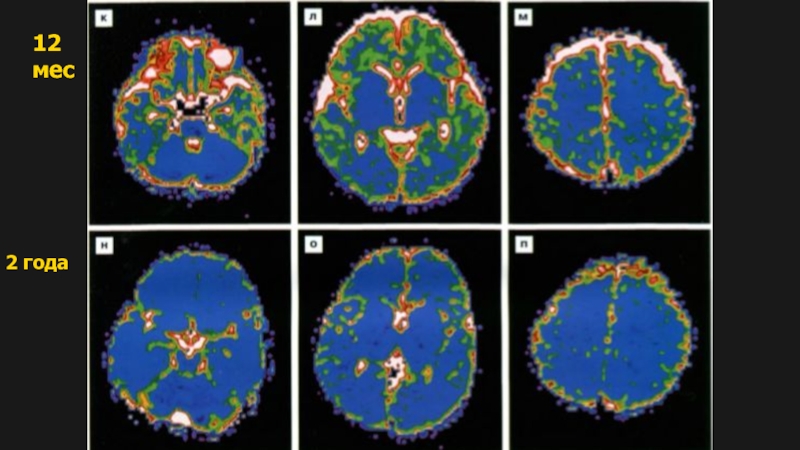

Слайд 1812 мес

2 года

12 мес2 года